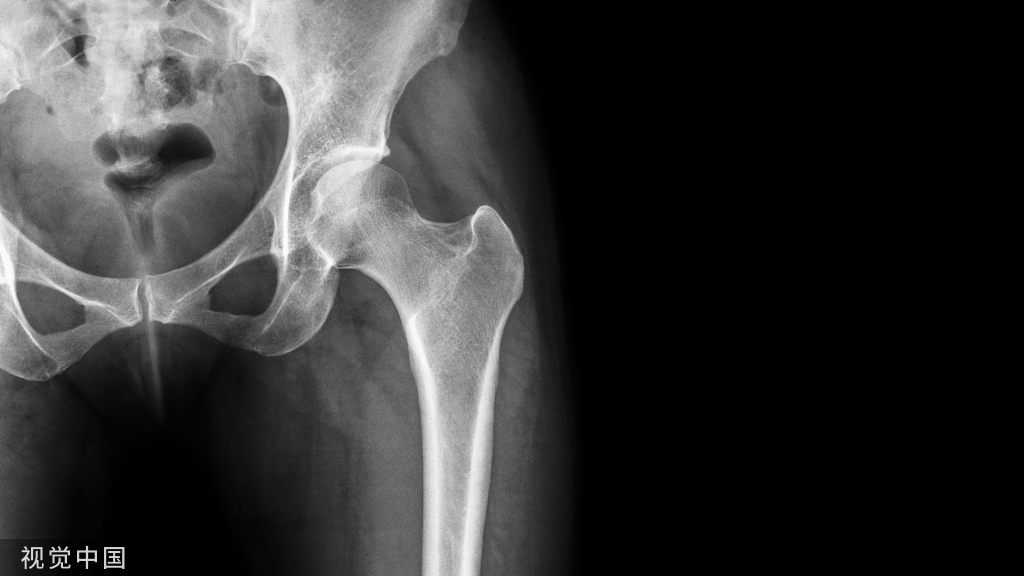

前交叉韧带的解剖

前交叉韧带(anterior cruciate ligament,ACL)起自于股骨外侧髁内侧面的半圆形凹陷处,然后经前内侧通过股骨髁间凹插入并附着于胫骨髁间隆起的前方,与外侧半月板的前中部相连;

股骨附着点位于股骨外髁的后内侧部,胫骨附着点位于胫骨髁间棘前侧与外侧半月板前角之间;

ACL走行比较陡直,倾斜角度至少应与Blumensaat线(股骨髁间窝皮质线,指股骨后侧面和ACL胫骨附着点之间的连线)相一致;

根据前交叉韧带胫骨附着点的位置将其分为前内侧束(anteromedial, AM)和后外侧束(posterolateral, PL)两部分。